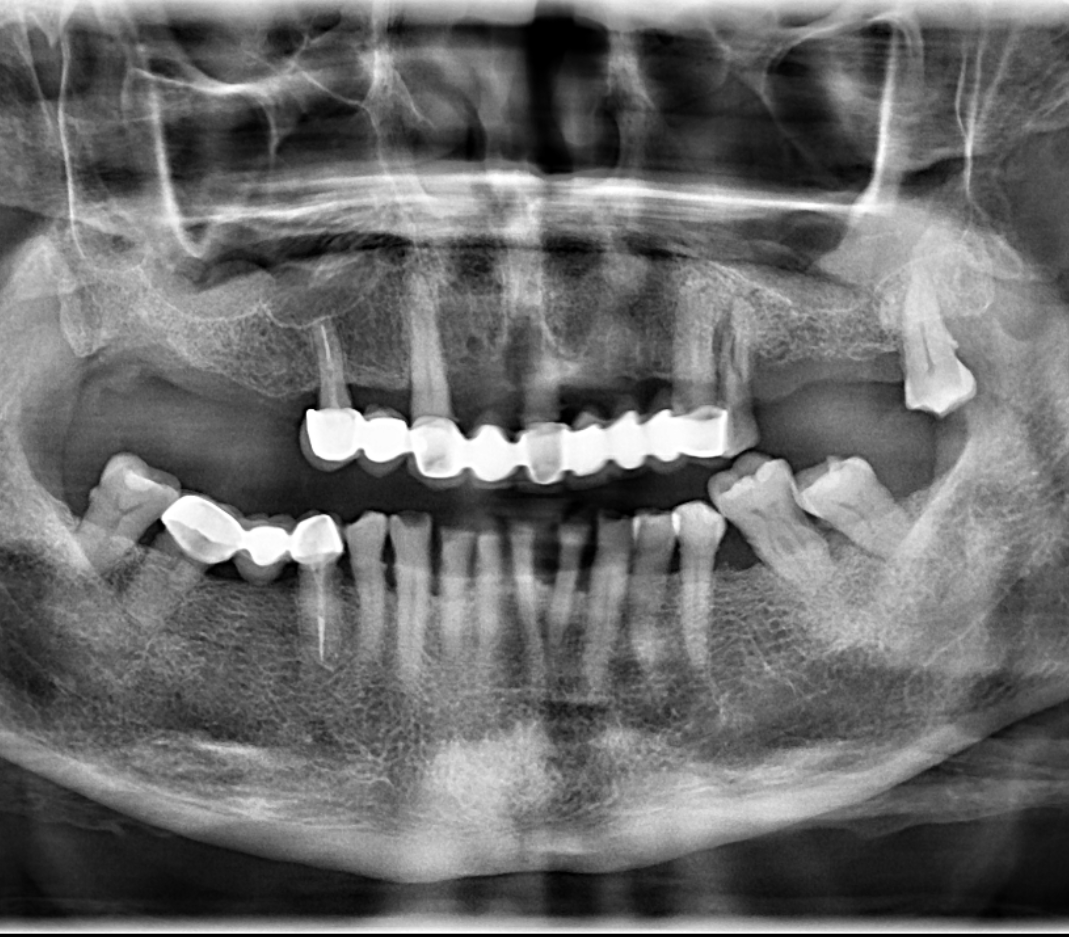

En la radiografía panorámica (Figura 1) se identificó, a nivel de la pieza 24, una línea radiolúcida de orientación diagonal, que se extendía desde la superficie cervicodistal hasta el tercio medio radicular mesial, asociada a un proceso osteolítico pararradicular adyacente. Adicionalmente, se evidenció reabsorción ósea generalizada, presencia de múltiples restauraciones coronarias y protésicas, así como atrición dental.

RADIOGRAFÍA PANORÁMICA